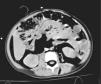

Figura 1.

Imagen mediante radiografía portátil de tórax y abdomen en la que se aprecia neumotórax derecho a tensión, neumotórax izquierdo, enfisema subcutáneo cervical y en pared lateral del tórax y neumorretroperitoneo.